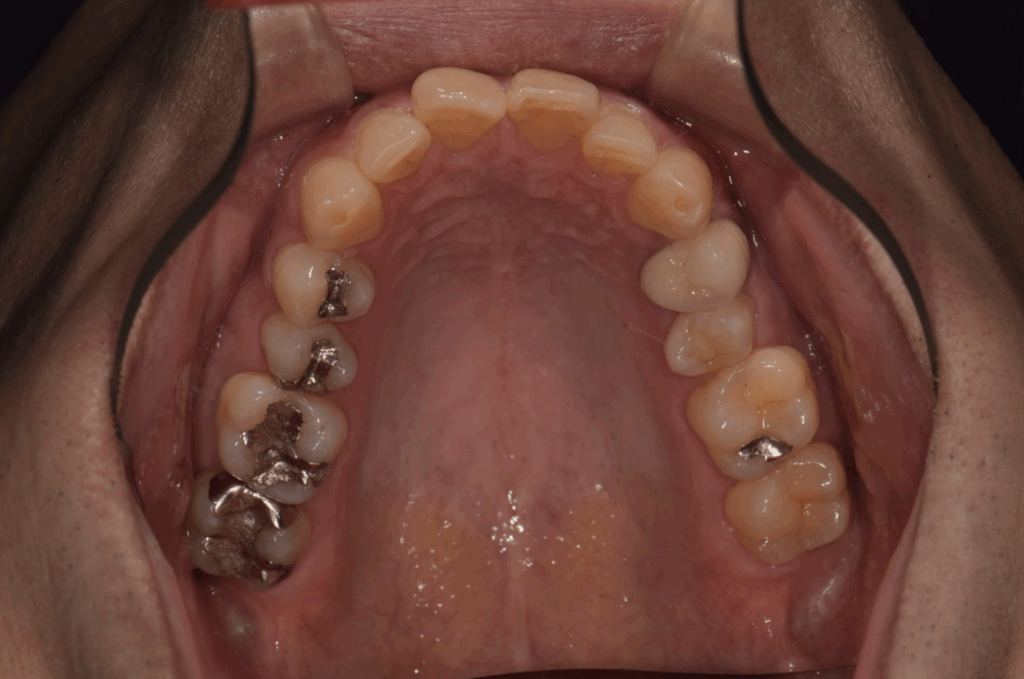

術前 右上7の銀歯